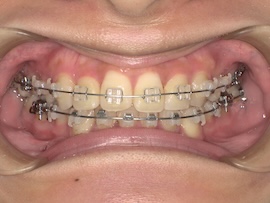

そして1ヶ月後、

左上の親知らずとその手前の歯の間に隙間があり、今は食事のたびにものが詰まります。

その隙間を閉じつつ左側の噛み合わせをより良くするため、再度ゴムかけをすることになりました。

写真にはないですが今回は左上の3番目(犬歯)と左下の7番目(一番奥)にゴムをかけます。以前左下は6番目でゴムかけをしていたのでさらにかけるのが難しくなりましたが、それでもやはりすぐに慣れるものです。

あとは正中(上下の前歯の真ん中)が合うようにも、最後のゴムかけをあと数ヶ月頑張ろうと思います。